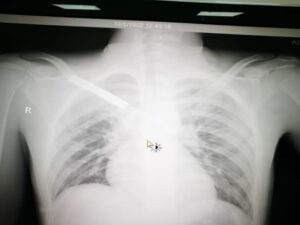

وأكدت أنه بعد إجراء الفحوصات السريرية والإشعاعية والمخبرية تبين وجود انفصال تام لعظم الترقوة مع عظم القفص الصدري بالإضافة إلى كدمات في الرئة وكسور في عظام الحوض وخلع في المفصل مما استدعى دخوله بشكل عاجل لغرفة العمليات الكبرى وإجراء عملية أمامية على الصدر شملت المفصل القصي الترقوي وعظم الترقوة اليمنى

وإزالة الضغط على القسم العلوي من الرئة والشريان والأوردة والأعصاب التي تغذي الطرف العلوي وتفريغ التجمع الدموي الناتج عن الخلع والكسر وإعادة الجزء المكسور من الترقوة من داخل القصي والربط بين الضلع الأيمن الأول والترقوة للمحافظة على ثبات المفصل، حتى استقرت الحالة لتنقل بعدها إلى غرف التنويم لاستكمال المتابعة الطبية لها حتى الخروج من المستشفى- بإذن الله- بصحة جيدة.